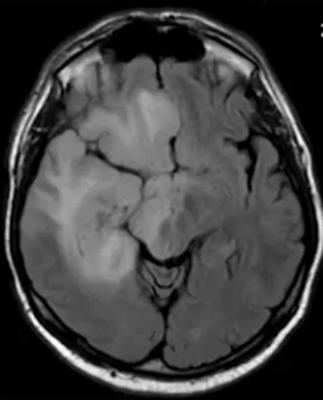

Эпендимома при МР-сканировании головного мозга

- эпендимомы — предположительно образуются в эмбриональном периоде. Характеризуются четкими контурами, плотнее, чем здоровые ткани, редко вызывают отек, чаще обнаруживаются в полостях желудочков;